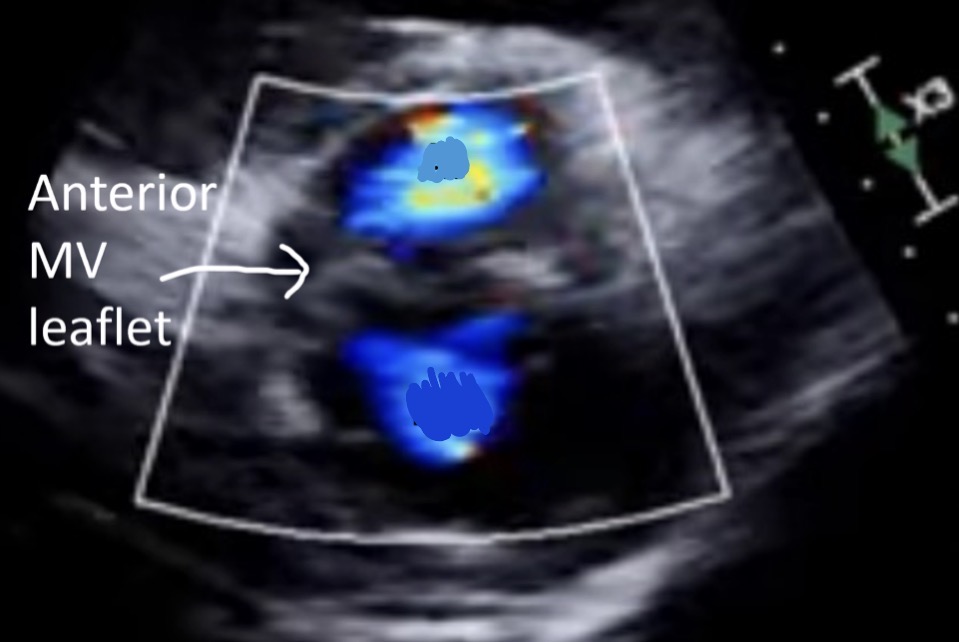

Anterior leaflet doming, RMS

What is the hockey stick sign and what pathology is it related to

Leaflet thickening, fish mouth appearance, hockey stick sign, chordal thickening

ECHO findings of RMS

Hockey stick sign, RMS

What is this image showing